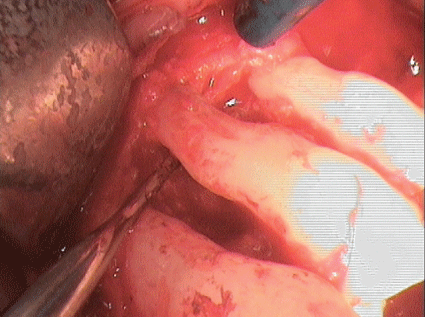

图11:光滑根面24和25,用超声骨刀技术完全去除肉芽组织。

图12:光滑根面24和25,用超声骨刀技术完全去除肉芽组织。

先前准备的全瓣显示手术部位在牙齿24和25周围有明显的垂直骨缺损;第24颗牙仅靠顶端附着在骨头上。根据现有的再生措施的证据,由于患者的高度顺应性,缺损被异种骨(Bio - Oss collagen, Fa。Geistlich)广泛开放刮除(光滑根表面,在超声骨刀技术的帮助下完全去除肉芽组织;(图11和12)以及pregel™和Emdogain®(Straumann GmbH)的应用。然后用可吸收的膜覆盖填充的缺陷。